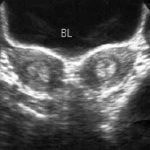

抗胚胎抗体是免疫性复发性流产患者体内的特异性抗核抗体,是诊断和鉴别诊断复发性流产的黄金标准,北京安太医院陈凤林院长的发明专利技术。抗胚胎抗体是妊娠早期胚胎细胞处于高度复制分裂,细胞核变成染色体,2号染色体上控制纤维连接蛋白的基因完全暴露,且功能活跃,恰逢其时的人工流产,子宫内膜受到创伤,胚胎细胞被破坏,纤连蛋白控制基因通过开放的子宫静脉进入母体,纤连蛋白控制基因作为抗原,刺激母体产生了对应的抗核抗体—抗胚胎抗体。所以特异性极高,几乎与妊娠的HCG相媲美。